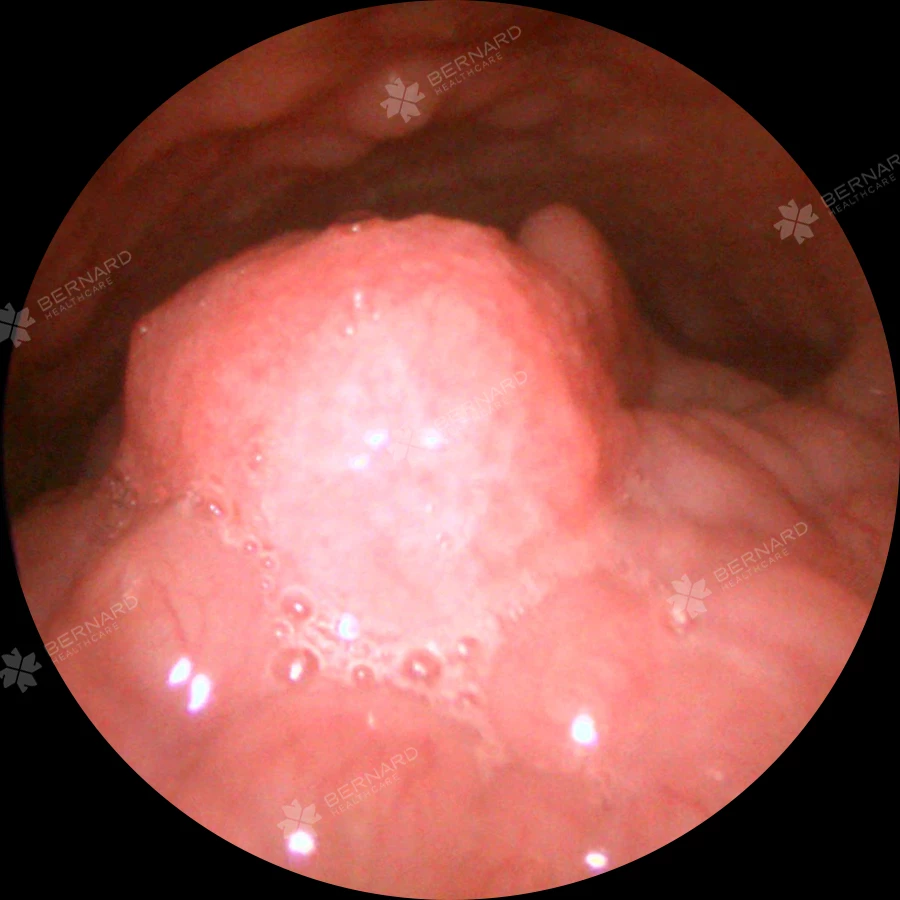

Lần này, anh T. tham gia khám sức khỏe định kỳ tại Bernard Healthcare theo chương trình chăm sóc sức khỏe doanh nghiệp. Mọi hạng mục kiểm tra ban đầu đều không cho thấy vấn đề gì bất thường. Nhưng khi đến phần nội soi Tai Mũi Họng, khu vực hạ họng và thanh quản, bác sĩ nhận thấy một chi tiết nhỏ nhưng đáng ngờ: u nhú tại nắp thanh môn bên phải, ở vị trí thanh nhiệt – xoang lê. Điều đáng nói là niêm mạc vòm họng lại rất sạch sẽ và không có dấu hiệu bất thường.

Phương pháp chẩn đoán chủ yếu dựa vào nội soi thanh quản, giúp bác sĩ quan sát trực tiếp vị trí tổn thương và đánh giá mức độ ảnh hưởng. Trong trường hợp nghi ngờ, bác sĩ có thể chỉ định sinh thiết mô bệnh học để xác định bản chất u nhú, từ đó lên kế hoạch điều trị phù hợp.